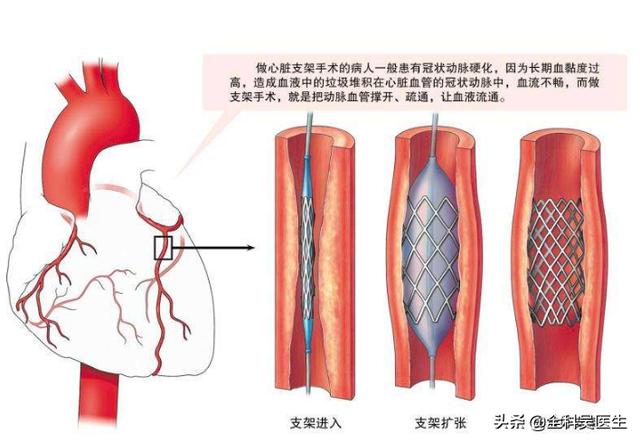

而今日の冠動脈性心疾患の主な治療法としての心臓ステント留置術症状の緩和、生活の質の向上、寿命の延長を達成しながら、多くの命を救ってきた。しかし、心臓にステントを入れることが大病を患うことだと言えるのだろうか?今日は皆さんに集まっていただいて、このテーマについてお話ししようと思います。

では、この心臓ステント手術はどのようなプロセスで行われるのでしょうか?

私たちは皆、多かれ少なかれ知っているはずだ。冠状動脈性心臓病とは、主に心臓の冠状動脈が狭くなる病気である。心臓に血液を供給する血管の狭窄は、心筋虚血や心筋壊死を引き起こす可能性があり、この狭窄を解消して冠動脈への血液供給を回復させるために、治療法のひとつは次のようなものである。何か支えとなるものを持っていく。それこそが、今、私たちが話しているブラケットなのだ。

では、ブラケットはどのようにして取り付けられたのだろうか?

ステップ1、パンク。末梢動脈を見つけ、この動脈から穿刺を行うが、最も一般的な選択は、手の付け根か太ももの末梢動脈を選択することである。

ステップ2、チューブの挿入。その末梢血管開口部からシースを挿入し、適切なサイズのシースを選択してガイドワイヤーを進め、冠動脈開口部付近の心臓までゆっくりと送り込む。

ステップ3:軌道を確立する。最初のガイドワイヤーは冠動脈より太いので、この時は細いガイドワイヤーを選んで冠動脈病変の遠位部を通過させ、まずバルーンで拡張しなければならない。

ステップ4:ステントを留置する。バルーンの拡張が完了したら、このガイドワイヤーに従ってステントを留置する。

これが心臓ステント手術の大まかな流れだ。 経験を積んだ。熟練した医師は、この手術を30分以上かけて行う!そのため、心臓ステント手術を専門とする医師にとっては、そうである。大きな作戦ではない。。

穿刺が成功した後、私は彼女に、大丈夫、それしか感じない、次に特別な不快感を感じることはないだろう、と言った。血管造影はうまくいき、99%の狭窄がある左回転枝血管が詰まりかけていることがわかった。ステント留置もうまくいき、血管は正常に戻り、血流も正常に戻った。

このような場合、閉塞した冠動脈がステントを入れて閉塞した血管を開き、心臓の血流を再建するのに適していれば、心臓血管系の医師は通常、心臓発作による心臓障害のリスクを減らすために、できるだけ早くステント留置術を薦める。 このような場合、ステント留置術は、心臓発作による心不全、あるいは長期間血液を供給できないことによる心臓の死を回避するための重要な応急処置である。このような場合、ステント留置術は、心臓が長期間血液を供給できなくなることによる心不全、あるいは心臓の死を回避するために重要かつ必要な応急処置である。

(1) 急性冠症候群:病院の胸痛センター(救急外来)で毎日診察される冠動脈性心疾患で最も多いのが急性冠症候群である。実際には冠動脈のアテローム性動脈硬化プラークが何らかのきっかけで不安定になり、プラークが破裂して血栓症を誘発し、血流が突然途絶えるか途絶えそうになり、心筋に突然血液が供給されなくなり、心筋梗塞が起こります。この時、狭心症が20分以上続き、ニトログリセリンを3回連用しても緩和されないことが多いので、注意が必要で、心筋梗塞の可能性があり、一刻も早く120番救急ダイヤルに電話する必要があり、2時間以内に病院に到着し、血管を開くのが最善で、最も効果的な方法の一つはステント留置術である。もちろん、ステント治療が行えない病院では、血栓溶解療法が禁忌でなければ、時間を稼ぎ、その後の診断と治療の機会を作るために、血栓溶解療法も選択肢となる。

心臓ステント留置術は心筋梗塞の救命処置であり、心臓発作を救うための最も安全で成功率の高い方法である。

心臓ステント留置術は、閉塞した血管にステントを挿入し、閉塞を解除することで心筋への正常な血液と酸素の供給を回復させ、心臓の正常な機能を維持するインターベンショナル手技である。ステント留置術は心臓内で行われ、異物が挿入されるため、多くの患者さんがステント留置術の安全性を心配している。実際、過度の心配は不要である。

まず、心臓ステント留置術を必要とする疾患という点では、確かに主要な疾患である。ステント留置術は、冠動脈疾患の治療や心臓発作の救済に用いられる一般的な治療法である。 冠動脈疾患の患者にとって、ステント留置術を行うほどでなければ、医師は安易な手術を勧めず、やはり薬物療法が中心となり、手術後も生涯薬物療法を続けなければならない。一般的に言って、ステント留置術が必要なのは、冠動脈の狭窄が70%以上の患者か、不安定狭心症の患者だけである。心筋梗塞患者にとってステント留置術は、血管の閉塞を速やかに解除し、心筋への血液供給を回復させ、狭心症を緩和し、心筋壊死を予防する重要な方法であり、一般に応急処置として必要とされる。重症冠動脈性心疾患と急性心筋梗塞は、ともに大きな病気であることがわかる。

第二に、ステント留置術そのものについては、患者は過度に心配する必要はない。ステント留置術は大病の部類に入るが、それ自体は成熟した手段であり、腫瘍摘出や臓器移植などの他の手術に比べ、成功率が高く、安全性も確実である。ステント留置術は低侵襲手術であり、人体への外傷も少なく、また、循環器科の手術の中で最も一般的なものであることから、ステント留置術はすでに極めて成熟した手術であり、専門病院で専門医が行う限り、成功率は絶対的に保証される。ステント留置の心配については、実はその必要はない。現在、臨床で使用されているステントのほとんどは、コバルト、クロム、ニッケルなどの合金製で、組織適合性に優れ、拒絶反応やアレルギーのリスクはない。さらに、ステントは時間とともに血管壁に埋め込まれ、血管と一体化していくので、患者がステントの位置ずれやズレを心配する必要もない。したがって、手術もステント自体も比較的安全である。